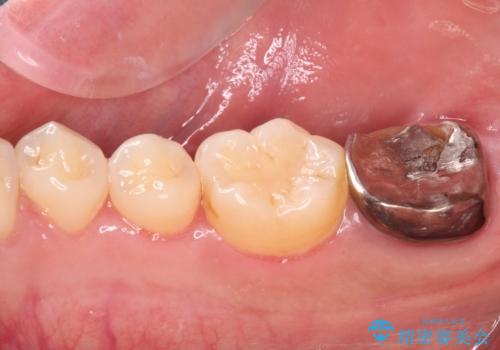

被せものが入れられない 外科処置を行ったセラミック治療

レントゲン撮影より、根尖部に病変が認められたため、根管治療を行った後に、歯冠長延長術を行うこととしました。

銀歯の頃は頻繁に外れていたため、不快感が強かったようですが、歯冠長を延長したことで外れにくいクラウンを装着することができ、不快感が改善されました。